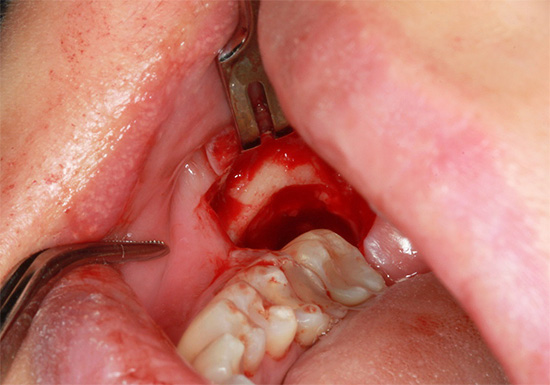

O principal significado da “complexidade” da remoção é pré-preparar o dente e, mais frequentemente, suas raízes, para extração com pinças ou elevadores. Para fazer isso, a parte da gengiva é excisada e o volume do tecido ósseo do orifício ao redor do dente é reduzido ou as raízes são separadas. Para esses fins, atualmente é usada uma broca com um conjunto de brocas especiais, além de vários instrumentos cirúrgicos adicionais.

Após coletar uma anamnese, os preparativos necessários para a remoção (por exemplo, remover uma pedra e placa de um dente sendo removido, enxaguar a boca com anti-sépticos fracos, etc.), a anestesia é realizada para tornar o processo de extração dentária indolor por um longo tempo. A remoção complexa pode levar de 15 a 20 minutos a 2-3 horas.

Depois de cortar as gengivas, separar as raízes com uma broca e extraí-las do buraco, o buraco é limpo de “sujeira”: resíduos de ossos, pedaços de dentes cariados, resíduos de raízes, serragem. Para fazer isso, as bordas afiadas do buraco são suavizadas com pinças de osso ou uma broca, a ferida é lavada com soluções anti-sépticas, um medicamento é colocado no buraco (de acordo com as indicações) e as bordas da ferida são suturadas. Recomendações são dadas ou é marcado um acompanhamento para monitorar a qualidade da cura.

A natureza da complexidade da intervenção é determinada pelo cirurgião-dentista em uma instituição especializada e, como observado acima, a remoção nunca começa sem um raio-X. A complexidade de sua remoção depende da natureza da localização do dente no orifício. Se o dente estiver localizado completamente no osso e quase estiver ao longo da mandíbula, a operação poderá demorar muito tempo, à medida que as gengivas forem excisadas, o osso será cortado com a separação da coroa e das raízes dos dentes, seguido de uma extração em fases do orifício ósseo.